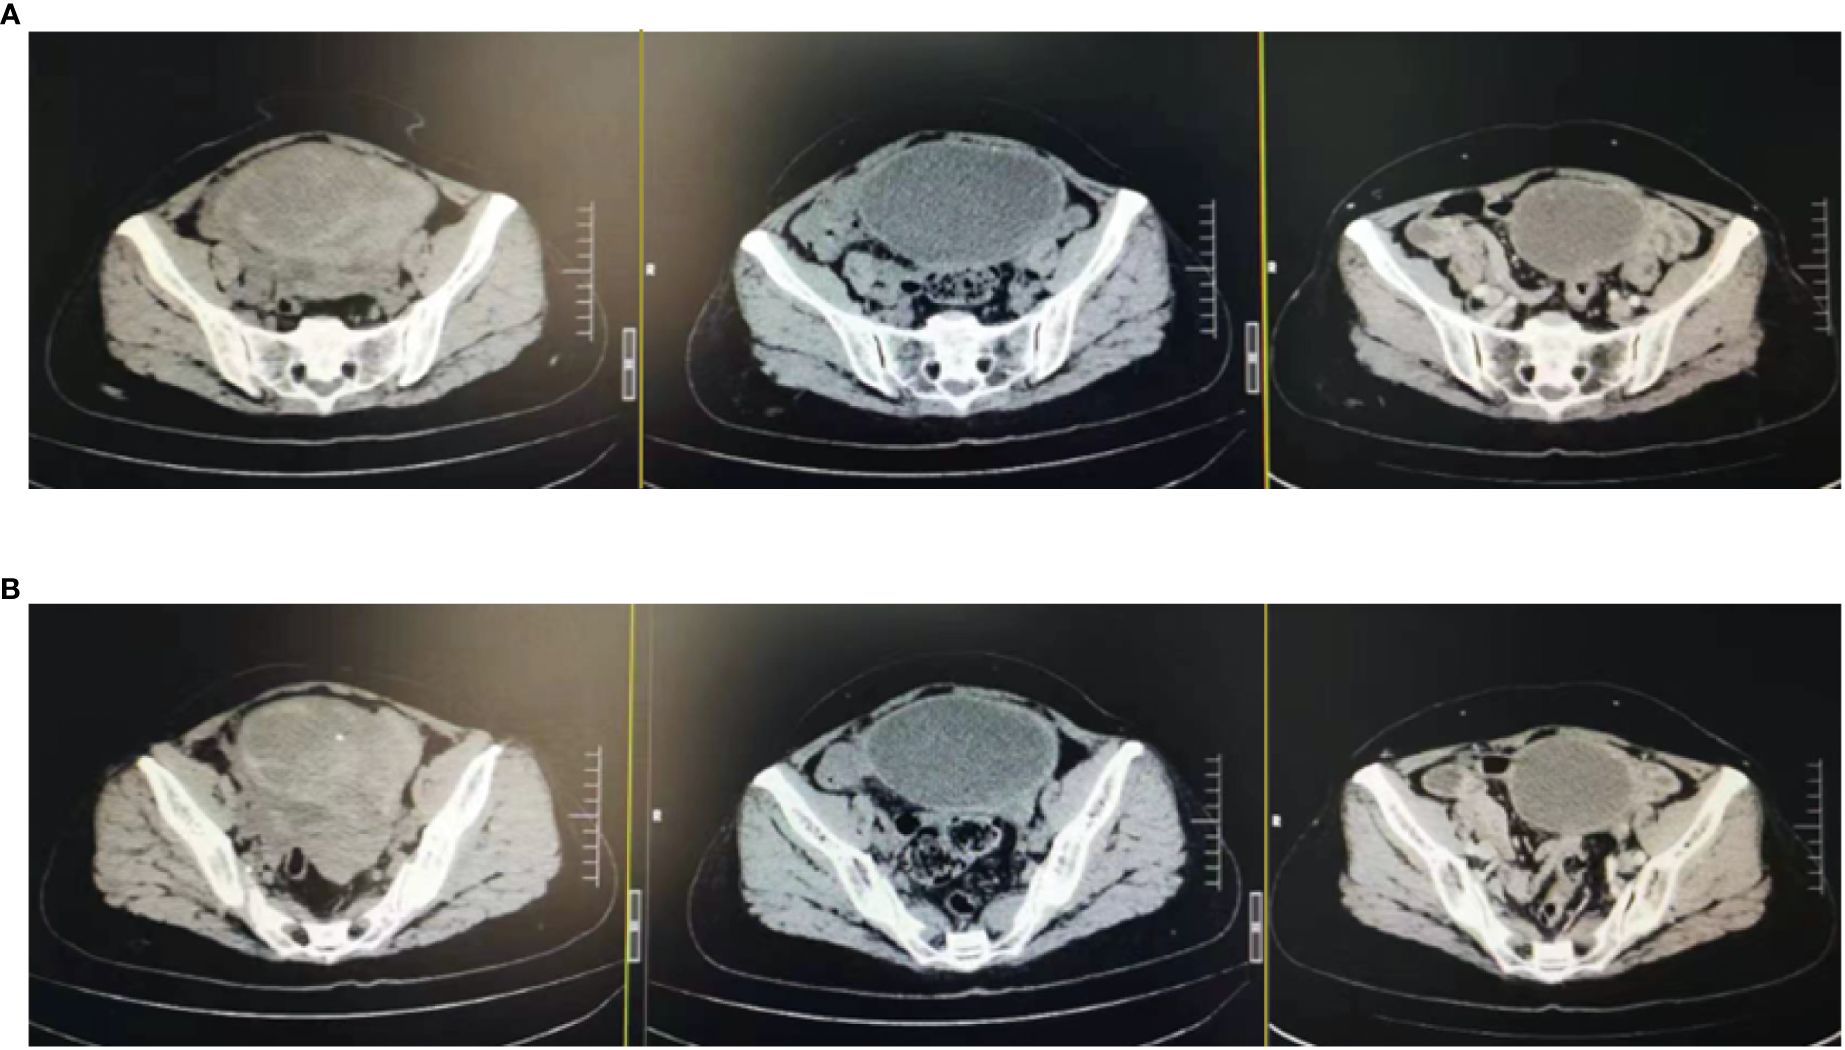

Figure 3

Changes in lesions: After the triple therapy, the CT showed a significantly smaller pelvic mass. (A) Pelvic mass before the triple therapy. (B) Pelvic mass after the triple therapy.